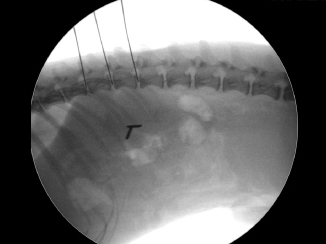

【診療科目】>神経科> 経皮的レーザー椎間板減圧術(PLDD)

椎間板ヘルニアの治療の中でも「体に負担が少ない」「傷口もほとんど残らない」がPLDD(Percutaneous Laser Disc Decompression)というレーザーによるヘルニア手術です。

傷はほとんどわかりません。Hansen2型に有効。